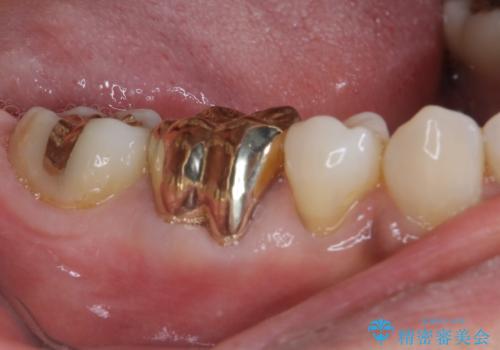

ゴールドは「白い歯」ではありませんが、銀歯の金属色とは異なり、非常にきれいな色合いが特徴です。

もちろん、適合が極めて良いという圧倒的メリットもゴールドクラウンやゴールドインレーの特徴です。